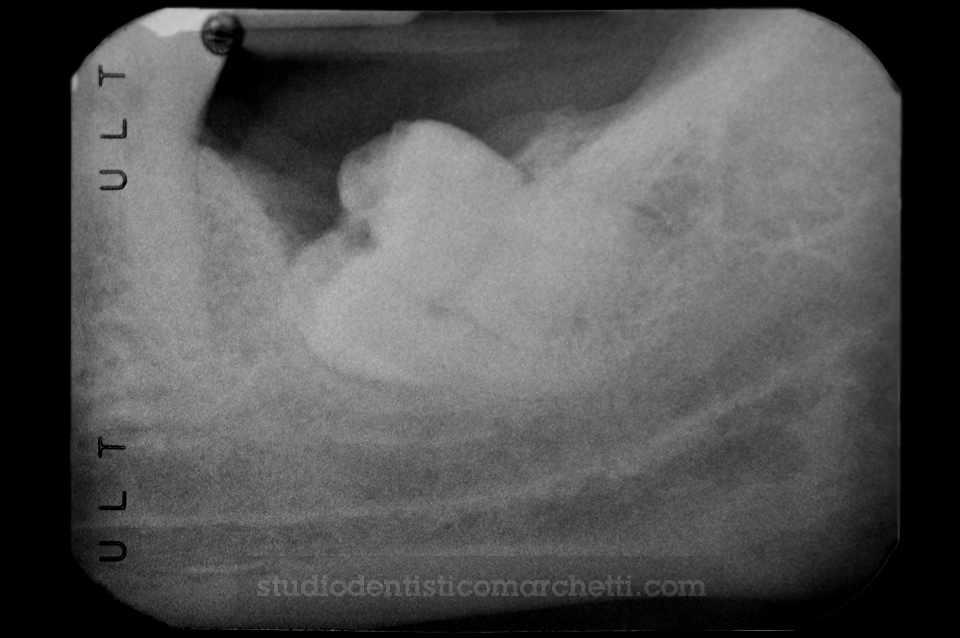

Chirurgia Orale

Estrazione di Dente del Giudizio Incluso

Chirurgia Orale

Estrazione di Dente del Giudizio Incluso

Chirurgia Orale

Estrazione di Dente del Giudizio Incluso